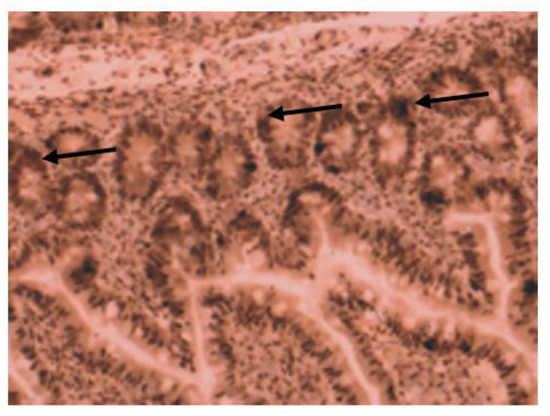

VDR Immunohistochemistry Expression Is Down-Regulated in Colorectal Cells of Patients with IBD and Could Rank the Patients According to Their Complications Risk

- VDR nuclear expression is significantly reduced in patients with IBD compared to controls;

- VDR down-regulation in patients with inflammatory bowel disease (especially patients with UC) could establish stratifying them into groups, regarding closer surveillance according to their risk for CAC;

- VDR expression could contribute in differentiating patients with IBD according to their specific diagnosis, into patients with UC and patients with CD, respectively.